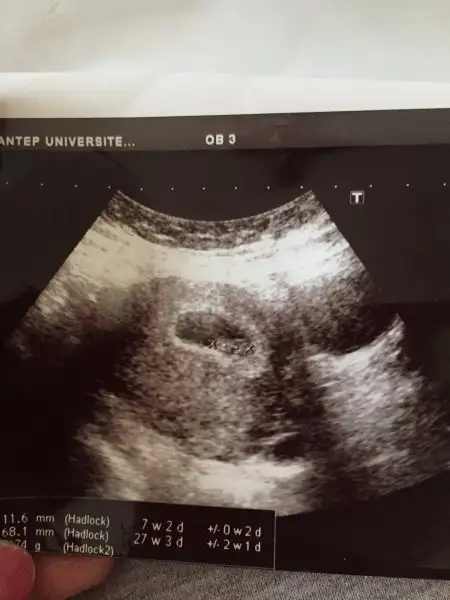

Bugün kontrolüme gittim çok şükür hamdolsun rabbime doktor iyiye gidiyor kese yukarı çıkmış dedi 7+2 dedi şuanda tam günü gününe gidiyoruz.kalp atışı var zaten dedi ama doyamadım miniğimi. Araştırma hastanesi olduğu için sadece önemli şeyleri söylüyorlar yani herhangi tehlikeli bi durum varmı yok mu ama sesini duymak için özele gidicem ayrıntılı anlatsınlar bakalım